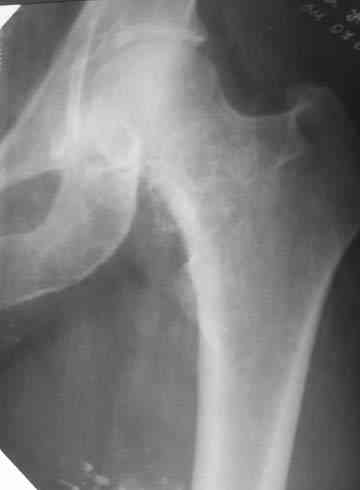

Боль постепенно усиливалась в течении последних 2 лет. Лечилась амбулаторно у невролога по месту жительства с диагнозом остеохондроз поясничного отдела позвоночника, корешковый синдром. В общих и биохимических анализах крови изменений не отмечалось, ревматоидный фактор (РФ), С-реактивный белок – в пределах нормы. Рентгенологическое исследование. В прямой и боковой проекции левого тазjбедренного сустава отмечается уплотнение крыши вертлужной впадины. В мягких тканях определяются округлой формы участки неравномерного обызвествления.Заключение. ДОА тазобедренного сустава. Хондроматоз слева в мягких тканях.Клиника. Видимых деформаций в области тазобедренного сустава нет. Ограничено отведение в левом тазобедренном суставе из-за болей до 20º. На основании клинических и лабораторных показателей был поставлен диагноз "Хондроматоз левого тазобедренного сустава". После стандартного предоперационного обследования выполнена диагностическая артроскопия тазобедренного сустава – обнаружены свободно лежащие внутрисуставные хондральные тела > 2 см в диаметре, хондромаляция хряща головки бедренной кости II степени. Выполнена боковая артротомия, внутрисуставные тела удалены, синовиальная оболочка частично резецирована. Послеоперационное течение – без осложнений. Швы сняты в срок, заживление первичным натяжением. Назначен курс лечебной физкультуры. Учитывая наличие рентгенологических признаков коксартроза, проведен курс внутрисуставной вискосуплиментарной терапии препаратами 1% гиалуроновой кислоты № 2.Осмотр через 1 месяц после оперативного лечения. Жалоб на боль при ходьбе нет, движения в полном объеме. Рекомендовано динамическое наблюдение раз в полгода и контрольная рентгенография через год